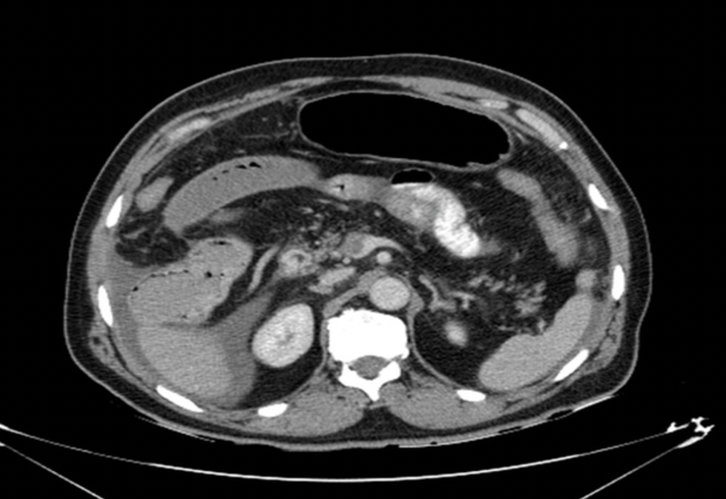

Caso clinico 2

Paziente con dolore addominale severo, lattati elevati. APR: Fattore V di Leiden.

Perché la parete intestinale appare ipodensa nonostante sia presente enhancement mucoso?

- Vasospasmo arterioso diffuso

- Necrosi mucosa selettiva

- Edema sottomucoso da congestione venosa

- Riduzione del flusso arterioso

- Presenza di aria intramurale

Risposta corretta: C

COMMENTO

Nell’infarto venoso:

- il problema è nel deflusso → ↑ pressione capillare

- stravaso di liquidi → edema sottomucoso

- mucosa può ancora captare inizialmente

Risultato:

- pattern “a bersaglio”

- centro ipodenso (edema)

- mucosa periferica con enhancement

Insight: arterioso ≠ venoso

- arterioso → parete sottile, ipoenhancement

- venoso → parete ispessita, edema marcato